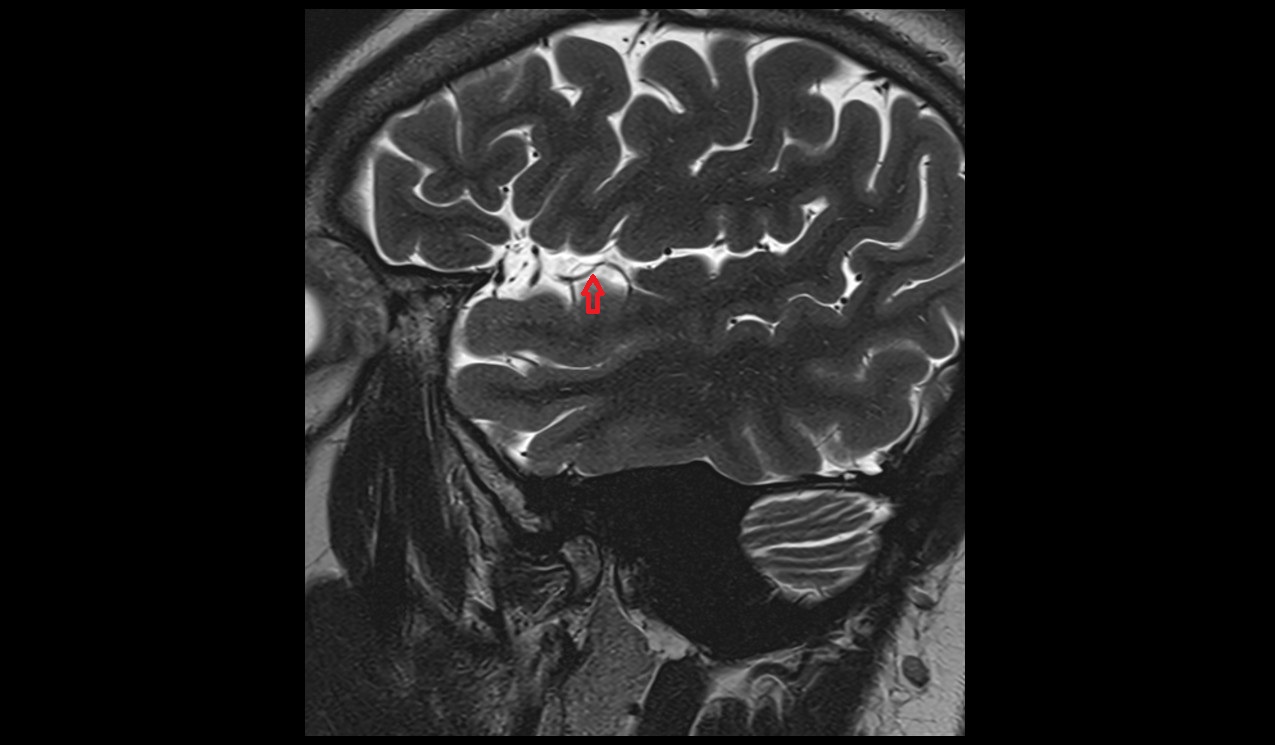

- Pituitary stalk

- Pituitary gland

- Anterior lobe of pituitary gland

- Posterior lobe pituitary gland